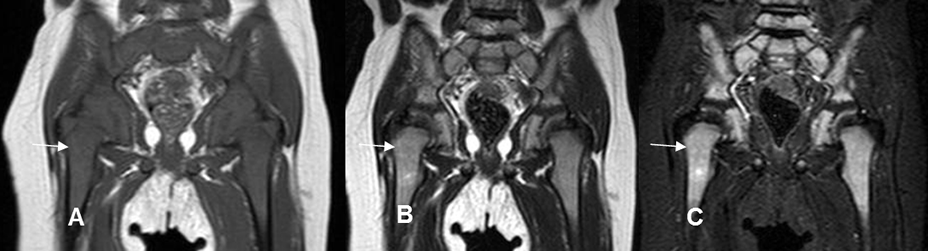

Fig 4 A. Medula ósea normal de un niño.

A: RM coronal en T1, B: RM coronal en T2 y C: RM coronal en STIR. Apariencia de la medula ósea en un niño, la cual es hipointensa en T1 e hiperintensa en T2 y STIR, por predominio el de la medula roja.